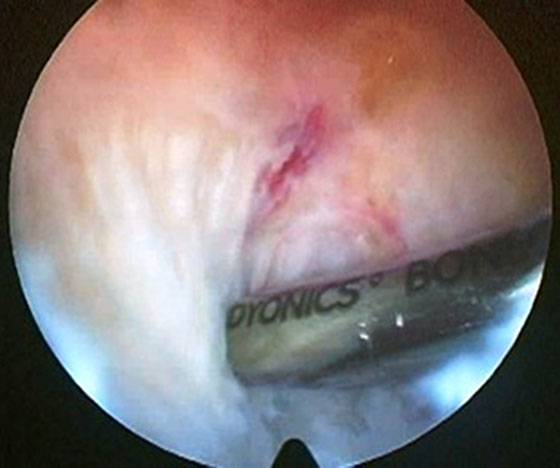

Se procede luego a realizar el portal posterointerno. Dado que no se reseca el remanente HPM, el espacio para acceder a la cápsula posterointerna se encuentra reducido, para ampliarlo realizamos una mínima “notchplastia” en la parte posterior del cóndilo interno (Fig. 4). Con la visión desde el portal anterointerno colocamos un switcher, de los utilizados en cirugía de hombro, desde el portal anterolateral ubicándolo entre el remanente ligamentario y el cóndilo interno (Fig. 5). Luego se pasa la cánula de irrigación guiada por el switcher y se accede con la óptica a la cápsula posterointerna, bajo visión directa colocamos una aguja espinal para localizar el portal, completando con bisturí para luego colocar la cánula de trabajo (Fig. 6). En este punto se vuelve a pasar el artroscopio al portal anterointerno, se introduce el shaver por la cánula del portal posterointerno, y se realiza la limpieza de la capsula posterior, siempre con la hoja de corte hacia anterior para evitar la lesión de estructuras vasculonerviosas. Se continúa alternando los portales anterointerno y posterointerno con visión, shaver, pinza basket y raspas de 90º, hasta completar la desinserción de cápsula posterior e identificar el remanente distal del ligamento sin afectar la inserción. En los casos en que la lesión ha sido en la sustancia colocamos la guía tibial distal a la inserción tibial (Fig. 7). Si la lesión ha comprometido la inserción tibial, levantamos la cicatriz que encontremos y colocamos la guía por debajo del remanente (Fig. 8). Para la introducción de la guía sin lesionar los remanentes ni el LCA se coloca la óptica en el portal anteroexterno y se controla el ingreso de la guía por el espacio entre el remanente y el cóndilo interno (Fig. 9). Se pasa el clavo guía, siempre cuidando de llegar en forma motorizada hasta contactar la cortical posterior y se completa el pasaje golpeando con martillo para evitar una salida brusca del mismo. Se pasa la fresa canulada del diámetro adecuado, protegiendo la emergencia de la misma con una cureta. Una vez completado el túnel tibial, se pasa un alambre o cable desde el orificio externo tibial hacia proximal, con visión en portal posterointerno, al ver emerger el alambre o cable por el orificio tibial posterior, se vuelve la óptica al portal anterointerno para controlar el pasaje de un grasper desde anteroexterno a través del intervalo entre HAL y LCA, y dirigirlo hacia posterior (Fig. 10); se vuelve con la óptica al portal posterointerno y se visualiza la recuperación del alambre o cable con el grasper hacia la parte anterior de la rodilla (Fig. 11). Se amplía el portal anteroexterno y se anuda la sutura tractora del injerto al alambre o cable, y traccionando desde el orificio distal del túnel tibial se hace ingresar el injerto en forma retrógrada a la articulación y, luego, al túnel tibial por su orificio posterior. En caso que se utilice el injerto de tendón cuadricipital la parte tendinosa irá al túnel tibial y el bloque óseo al femoral. Una vez ingresado el injerto al túnel tibial, se vuelve la óptica al portal anterointerno, en el portal anteroexterno tendremos la sutura tractora del extremo “femoral del injerto”, es aconsejable en este punto llevar el injerto lo más distal posible para tener mejor visión articular, enhebrar la sutura tractora en una cánula de unos 6 mm de diámetro, para asegurarse que la sutura tractora y la clavija pasasutura pasan por el mismo espacio sin incluir tejido sinovial o grasa retrorrotuliana (Fig. 12). Se procede a pasar la aguja pasasutura por el túnel femoral, saliendo por las partes blandas de la parte medial de la rodilla, se tracciona y se asciende el injerto colocándolo en el túnel femoral. En caso que el injerto tenga bloque óseo puede ser necesario redirigir el mismo para ubicarlo en el túnel femoral, para esto ubicamos la visión en el portal anteroexterno y por el portal anterointerno utilizamos el trocar romo o el palpador para realizar una polea y mejorar la tracción para que ingrese el taco óseo en el túnel femoral (Fig. 13). Luego se realiza la fijación femoral con tornillo de interferencia de titanio o biodegradable. A continuación liberamos el manguito neumático, porque creemos que produce un espasmo en los isquiotibiales que dificulta la reducción de la tibia, dejamos pasar unos minutos que utilizamos para colocar un tornillo maleolar con arandela, distal al orificio externo del túnel tibial para realizar una segunda fijación de la parte tibial. Preferimos hacerlo antes de colocar el tornillo interferencial, porque esto generará una presión hacia posterior de la tibia. Se realiza la reducción tibial en 90° de flexión de la rodilla, se tracciona del injerto y se coloca el tornillo de interferencia tibial, luego la sutura remanente (polyester 5) se anuda en el tornillo maleolar completando la 2da fijación. Por último se constata con una nueva visión articular la posición y tensión del injerto (Fig. 14).

Figura 5